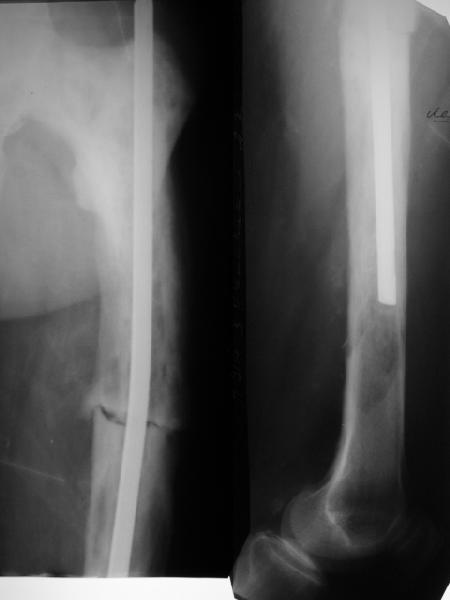

Мужчина 76 лет в феврале оперирован в одной из горбольниц - открытый интрамедуллярный остеосинтез бедра, травму получил при падении. К нам поступил с болью и ощущением подвижности в месте перелома, особенно при ротационных движениях. На снимках, кроме несращения, еще и изменение костной структуры. Чем оно обусловлено? Это не болезнь Педжета?Планируем бедро закрыто перештифтовать. Должно ли это состяние кости как-то повлиять на план? Рассверливать ли канал? Насколько? Гвозди есть от 9 до 12 мм.

I believe its Pagets. The bone looks larger than normal, along with coxa vara, which is characteristic. Check his alkaline phophatase. In rare instances, you can see aggressive lytic disease (unlikely here), which requires medical Rx to quiet down. Get out your reamers, and put

a big nail in him- the biggest his canal will take. Make it longer, and lock if you don't believe the fixation is snug.

>From the appearance of the x-rays and the description of a fracture after minimal trauma, I would be very concerned about a neoplastic

process. Odds would favor something metastatic and appearance might suggest a combined blastic-lytic lesion. I am particularly concerned about the lytic appearance distal to the end of the rod. I would work up the patient for both neoplastic and metabolic process before proceeding.

The femur is Pagetic.

Aim to use a strong reamed locked nail, as the femur is bowed and union may be slow.

Be prepared for greater than usual blood loss.

I think it could be a neoplasy (i.e. a giant cells sarcoma, infact the cortex seems to be thinner or destroyed.). Then the fracture you've seen synthesized with a nail could be a pathologic one. I see on x-rays a destruction of the medullary cavity too.